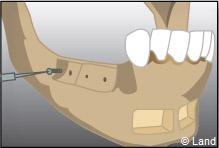

Les différentes étapes :

Prélèvement du greffon au niveau du site donneur

Apposition et stabilisation du greffon.

Apposition et stabilisation du greffon.